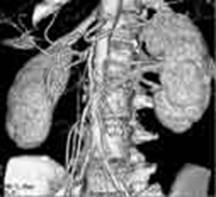

Fig. 3. Angiografie CT

Aorta si vascularizatia arteriala renala